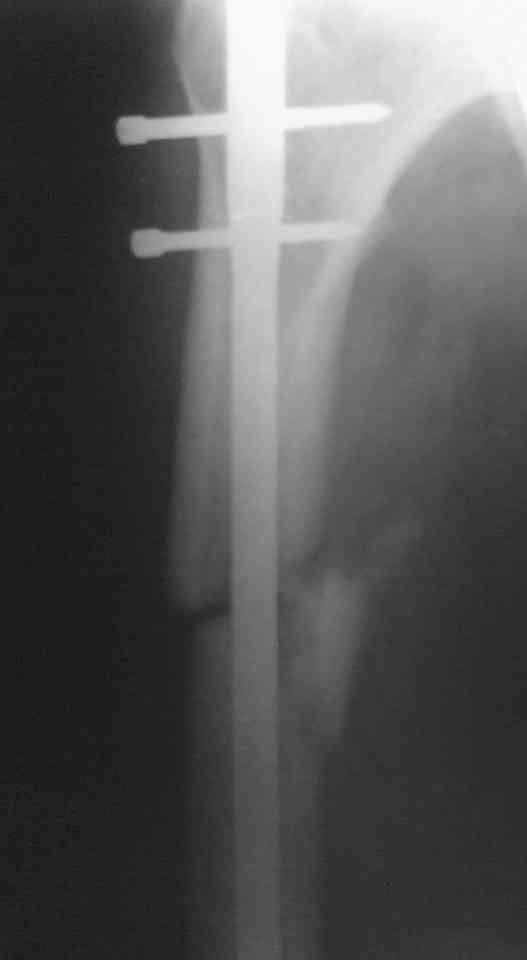

Мужчина 38 лет, получил травму ДТП 26.07.05, был оперирован 12.08.05(снимки 1 и 2), денамизация - февраль 2006. ( 3 и 4 снимки) на сегодняшний день (снимок 5)

беспокоит боли в тбс, и хромота.

клинически ходит самостоятельно с клюшкой прихрамывая. отмечается наружная ротация ниж. конечности. укорочение на 3,5 см.

сгибание и разгибание в тбс в полном объеме, ограничение ротации и отведения. объем движения в к\с полный.